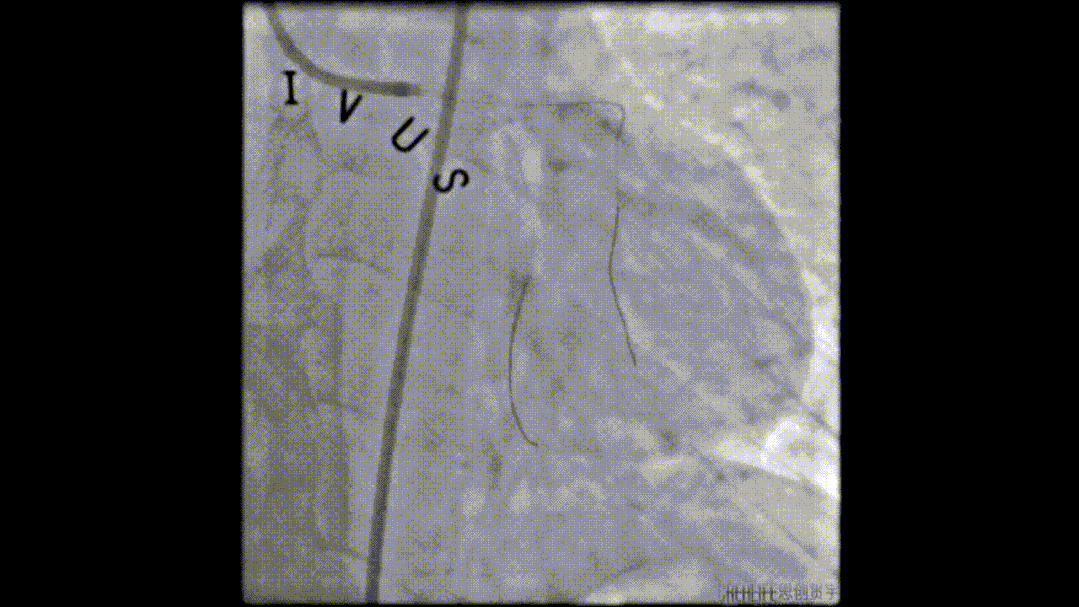

术前造影图像